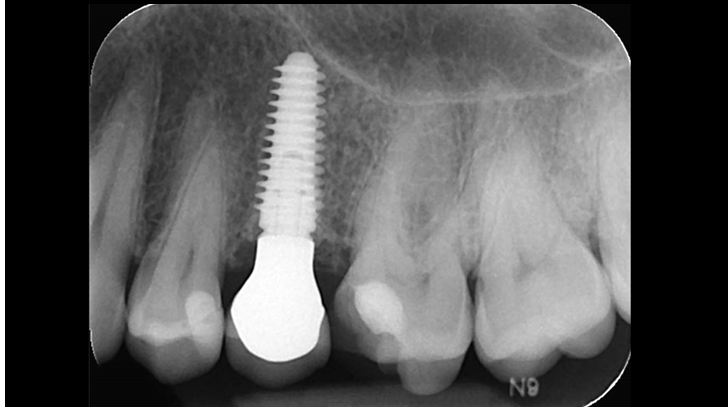

Clinical case: Extraction, immediate implant placement, & provisionalization

- Courtesy of Dr. Iulian Filipov, Romania -

Keywords

AnyRidge, R2GATE, guided surgery, immediate placement, immediate provisionalization, initial stability, Dr. Iulian Filipov, #25, maxillary posterior, immediate loading, Mega ISQ

Products:

AnyRidge implant system, R2GATE, MEGA ISQ, Digital prosthesis